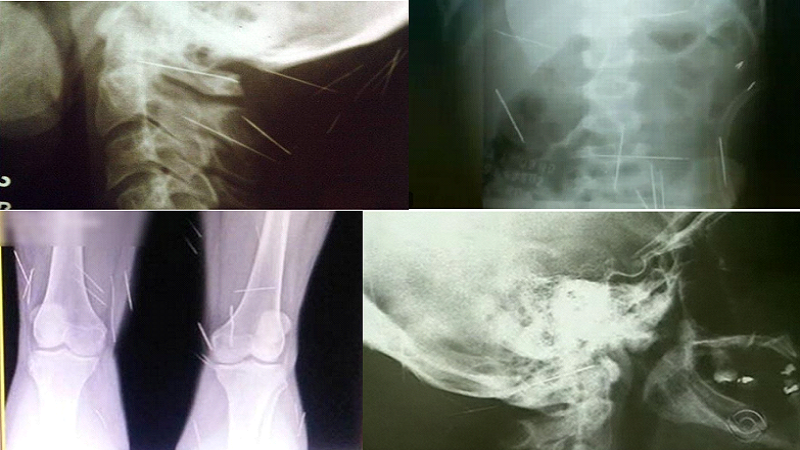

APORTE DE AGULHAS

APORTE – Número 1